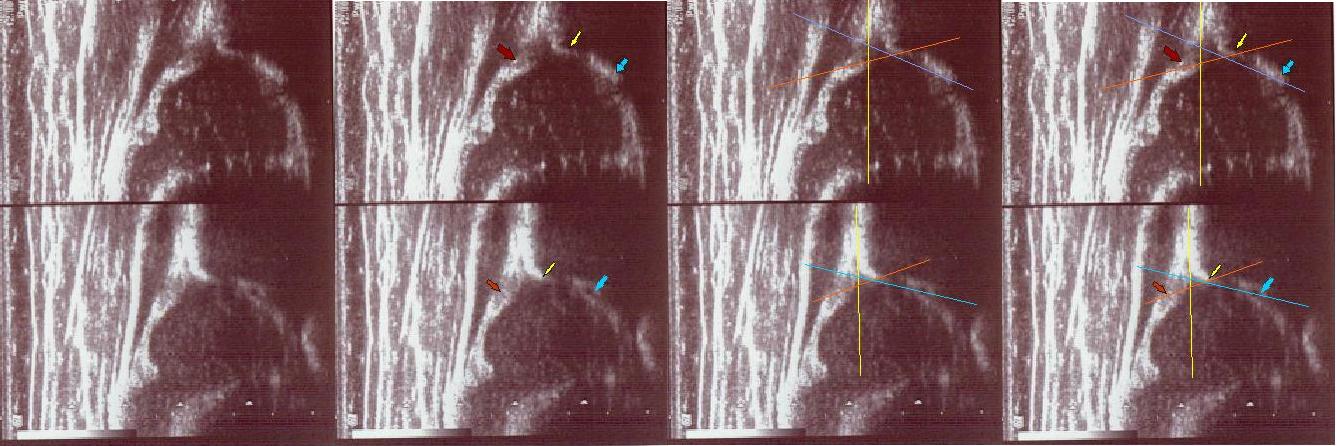

typIIa 6tyg.ż. dach kostny wystarczajacy;brzeg kostny kanciasty(mimo dysplastycznej panewki) pierwsza część dachu dobra , druga głębsza dalsza stroma(trzeba na to uważać) ;dach chrzestny pokrywa

górne zdjęcia strzałki pokazują obrabek(czerwona):brzeg kostny (żółta);gałąż dolna(niebieska) ,

prawidłowy przebieg linii dachu kostnego(niebieska) stycznie do echa gałęzie dolnej i echa brzegu kostnego ;

linii dachu chrzęstnego (pomaranczowa) stycznie do brzegu kostnego i przez środek geometryczny obrąbka i

linii podstawnej ( żółta)równolegle do sylwetki kości biodrowej po zewnetrznej stronie prze punkt gdzie ochrzęstne przechodzi w okostna i styka

sie z echem kości

dolny staw prawidłowy Typ I dach kostny dobry;brzeg kostny tępy ;dach chrzestny pokrywa

dolne zdjęcia

strzałki pokazują obrabek(czerwona):brzeg kostny (żółta);gałąż dolna(niebieska) ,

linii dachu chrzęstnego (pomarańczowa) stycznie do brzegu kostnego i przez środek geometryczny obrąbka i

linii podstawnej ( żółta